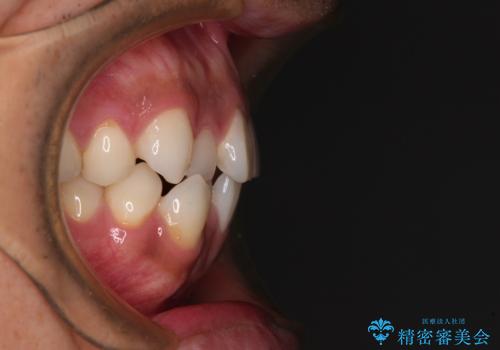

- 上下顎歯列のデコボコを改善したいとのことで来院された患者様です。

一年と数か月で矯正を終えることができました。